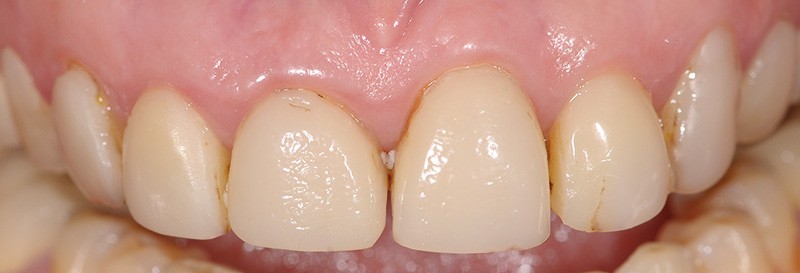

Avant de répondre aux différentes interrogations cliniques, il faut analyser la situation par des évaluations cliniques (état coronaire, situation endodontique, environnement parodontal) (fig. 1) puis, parfois, il est nécessaire de poursuivre cette étude préthérapeutique à l’aide d’outil de simulation comme l’articulateur (fig. 2), de techniques radiologiques en 3D. La conjugaison du recueil des informations et de l’analyse de la situation va nous permettre de proposer une solution en rapport avec la problématique médicale globale.